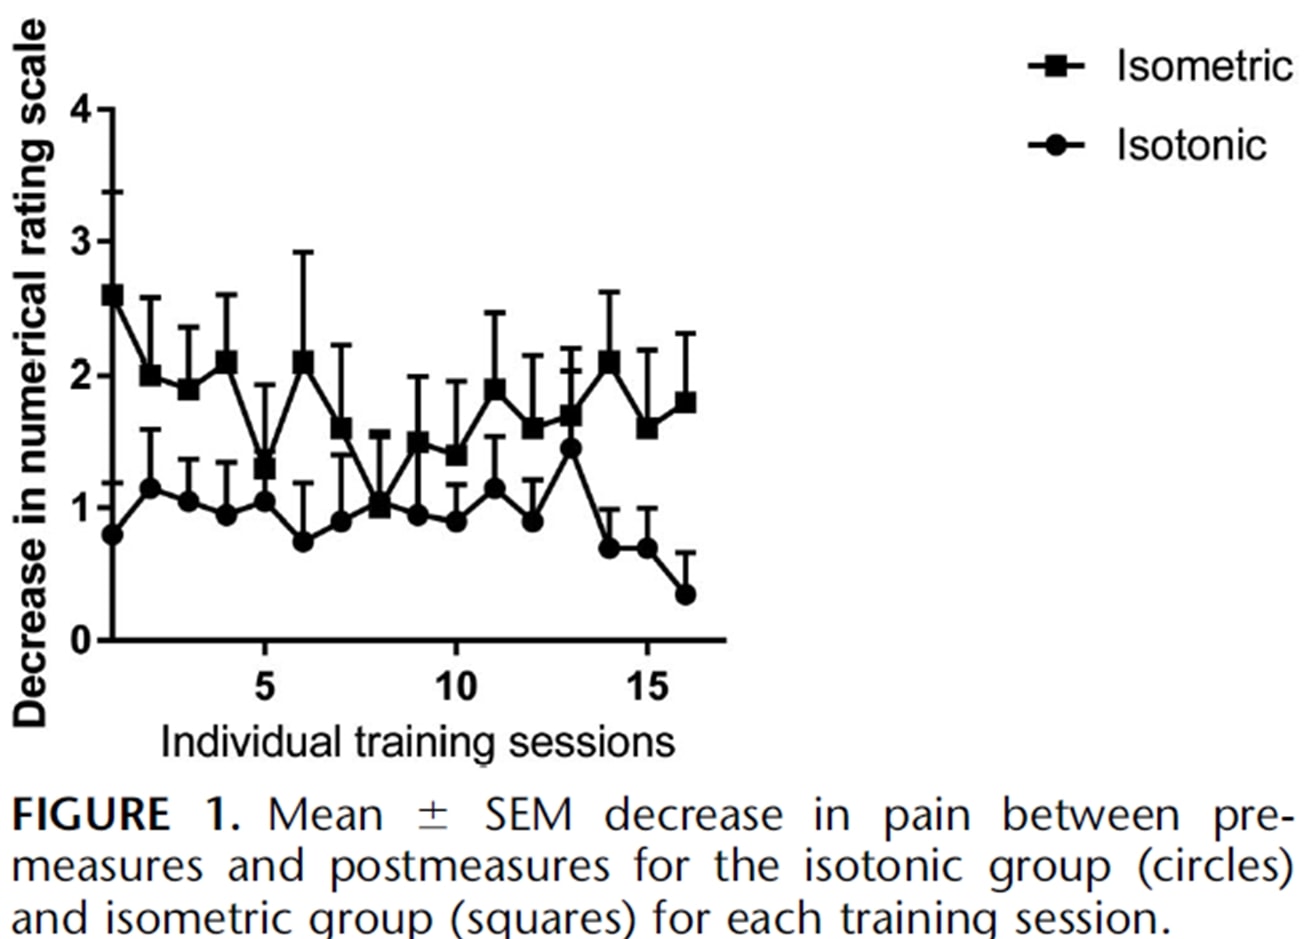

Dieselben Autoren führten zwei Jahre später eine Folgestudie mit springenden Athleten durch (Rio et al. 2017), in der sie ein isometrisches Programm und ein isotonisches Programm miteinander verglichen. In dieser Studie waren die Ergebnisse bei beiden Gruppen etwas uneinheitlicher, wobei die isometrische Gruppe eine stärkere unmittelbare Schmerzlinderung verzeichnete:

Eine aktuelle Studie von Holden et al. (2019) untersuchten ebenfalls die Wirkung von Isometrics bei Patellarsehnenentzündung und fanden keine schmerzlindernde Wirkung:

Abbildung aus Holden et al. (2019)

Der hohe Frauenanteil und das relativ hohe Durchschnittsalter sind jedoch untypisch für die Patellarsehnenerkrankung, die normalerweise eine Erkrankung junger, springender Männer ist. Es könnte also sein, dass die Diagnose einer Patellarsehnenerkrankung in einigen Fällen nicht korrekt war. Diese beiden Studien wurden zwar für die Patellarsehnenerkrankung durchgeführt, aber wir sollten prüfen, ob sich diese Ergebnisse auch auf andere Sehnen übertragen lassen.